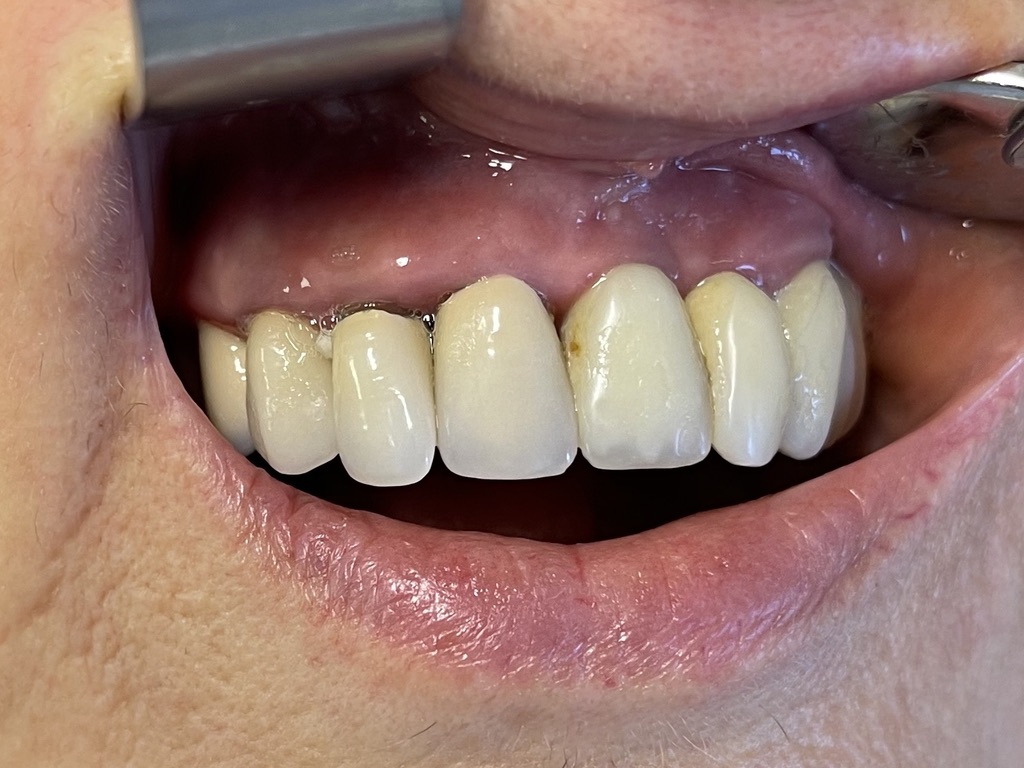

2 - AESTETICS AND FUNCTION IN HUMAN IMPLANTOLOGY

ABOUT AESTETIC PERFECTION...